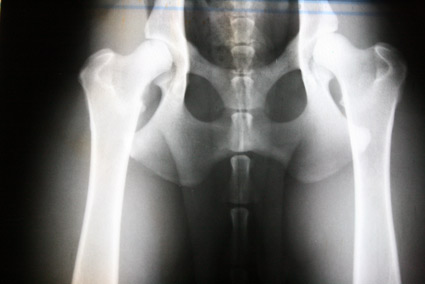

| HD:E/HD-schwer/HD 4-5 |

E/1 |

= Grad3 (schwer) |

HD-4 |

schwer |

Das gesamte Gelenk ist stark verändert, evtl. eine vollständige Luxierung, NORBERG-Winkel unter 90 Grad |

E/2 |

= Grad4 (sehr schwer) |

HD-5 |

sehr schwer |